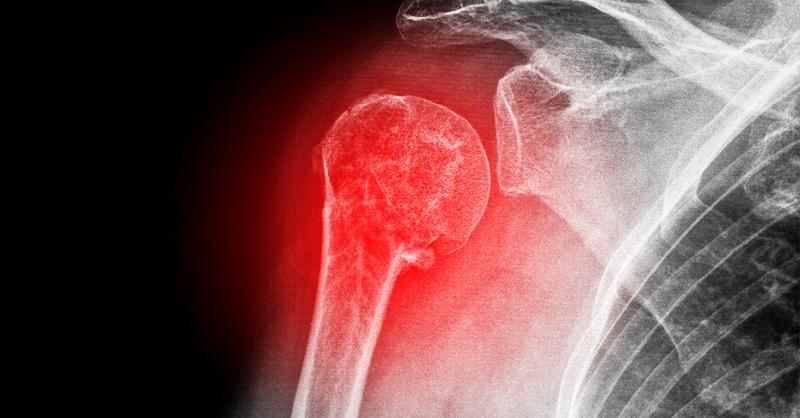

ACJ fixation techniques versus coracoclavicular ligament fixation/reconstruction techniques for Acute Rockwood Grade III Acromioclavicular Joint Dislocations

Acromioclavicular joint (ACJ) injuries make up about 9% of all shoulder girdle injuries and are frequent in young, active adults (1). According to the research, the incidence rate is significantly greater among adolescent athletes who play throwing and contact sports like rugby, football, and wrestling (where shoulder injuries can account for up to